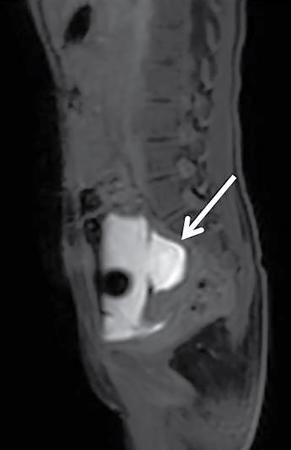

Anmol Bhatia, Kushaljit Singh Sodhi, Akshay Kumar Saxena Congenital as well as acquired anomalies of the bladder and urethra are a significant cause of morbidity in children. Various radiological investigations for imaging bladder and urethra include ultrasonography (US), voiding cystourethrography (VCUG) and intravenous urography (IVU), computed tomography (CT), magnetic resonance imaging (MRI) and contrast-enhanced voiding urosonography. In this chapter, we will discuss and illustrate a wide spectrum of congenital and acquired anomalies of bladder and urethral in children. Foetal allantoic stalk is the connection between the bladder dome and the umbilicus during the embryogenesis. Normally, it gets involuted by the second month of gestation. Depending on the degree of the persistence of this foetal allantoic stalk results in varying types of urachal remnants. The clinical presentation depends on the type of urachal remnant: Fluoroscopy is the best imaging modality for documenting the patency of urachus. However, there may be an underestimation of the exact length of the urachal remnant as inflammation occurring along the tract may block its lumen. CT and MRI are usually not needed for the detection of urachal remnants. However, urachal remnants are usually detected incidentally on CT scan done for other indications. Cystic or solid elongated tubular structure may be seen extending from bladder dome to umbilicus. A focal cystic lesion (Fig. 10.11.3) may be seen in the midline anywhere from bladder dome to umbilicus. In case the urachal remnant present with the symptoms, resection of the entire tract is warranted. Bladder diverticulum are localized outpouching from the bladder wall. They can be single or multiple of varying sizes. A male predominance is seen in comparison to females. It has been traditionally classified into four types: They can be incidentally detected or present with complications including recurrent UTI, urinary retention, incontinence, stone formation, VUR and bladder or ureteric obstruction. Bladder diverticulum should be differentiated from ‘bladder-ears’ in newborn male which is bilateral protrusion of bladder wall into inguinal ring. These are transient and disappear with growth. Appearance of diverticulum depends on cause, location, size and presence of complication features. VCUG under fluoroscopy is most efficient method to demonstrate diverticulum. Fluoroscopic monitoring during all phases including voiding and immediate postvoiding phase is important along with oblique and lateral views. Contained contrast-filled outpouching is seen which may be visible only during voiding phase when urine is forced into diverticulum during bladder contraction. Associated VUR is present in 50% of cases. Round or oval anechoic structure arising in communication with the bladder is seen. Well-defined homogenous structure with fluid attenuation/signal intensity arising from bladder wall (Fig. 10.11.6). Secondary complications like stone formation or rupture can be seen. Surgical removal using intravesical, extravesical or combined approach may be performed along with meticulous repair of bladder wall. Urinary bladder neoplasms are not commonly encountered in children. The majority of bladder neoplasms in children are of mesenchymal origin and overall rhabdomyosarcoma is the most common malignancy (Table 10.11.1). They can be incidentally detected or present with urological symptoms including dysuria, haematuria, incontinence and lower abdominal pain. It can manifest as filling defect in MCU studies done for other indications. Ultrasound is usually the first line investigation with cross-sectional imaging being performed in suspected cases for accurate characterization, localization, disease extent and complication. Histopathological analysis is often needed for final diagnosis. The differential diagnosis of bladder masses includes masses arising from adjacent pelvic structures, variants like ureterocoele or urachal remanent, mass forming cystitis (eosinophilic cystitis, BK virus–associated cystitis), haematoma, calculi or iatrogenic materials (e.g. Deflux used in VUR surgeries). Rhabdomyosarcoma Leiomyoma Neurofibroma IMT Leiomyosarcoma Angiosarcoma Haemangioma Urothelial carcinoma PUNLMP: urothelial papilloma Fibroepithelial polyp Paraganglioma Nephrogenic adenoma PUNLMP, papillary urothelial neoplasm of low malignant potential. Rhabdomyosarcomas are the most common urinary bladder neoplasms in first two decades of life presenting typically at ages 2–6 years and 15–19 years. Syndromic association with Li–Fraumeni cancer syndrome, NF type 1, MEN 2A has been found; however, majority are sporadic in origin. Histological subtypes include embryonal rhabdomyosarcoma (classical, botryoid and spindle cell variant), alveolar and undifferentiated sarcoma types of which embryonal form accounts for 90% of all cases. Locoregional spread to adjacent organs, muscles, regional lymphnodes is seen with distal metastasis to lung, cortical bones and retroperitoneal lymphnodes. Metastasis is found in approximately 10%–20% of patients at time of initial presentation. Overall survival and outcome depend on patient age and histological subtype with patients between 1–9 years of age and embryonal subtype having a better prognosis. Imaging work-up includes CT or MRI pelvis for local disease characterization and extent, CT chest, bone scintigraphy or FDG-PET for metastasis and staging. They commonly arise from bladder trigone and neck area. Ultrasound: They are typically large, intraluminal, multilobulated masses with well-defined margins and homogenous hypoechoic or hyperechoic echotexture. Foci of necrosis or haemorrhage are often seen. Vascularity on colour Doppler is increased. Hydronephrosis and bladder neck obstruction secondary to mass can be found. CT: Bulky heterogenous low attenuation mass that may invade into periurethral or perivesical tissue (Fig. 10.11.7). Calcification is rare.